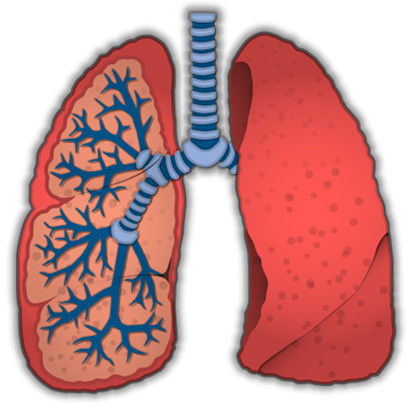

폐렴에 걸리면 폐가 염증으로 인해 제대로 기능하지 못하게 되므로 호흡이 어려워질 수 있습니다. 특히 가벼운 활동 후에도 숨이 차거나, 심한 경우에는 편안히 앉아 있어도 호흡이 힘들어질 수 있습니다.

폐렴에 걸리면 가슴에 통증을 느끼기도 합니다. 이 통증은 깊은 숨을 들이마시거나 기침을 할 때 더욱 심해질 수 있습니다. 폐에 염증이 생기면서 가슴 부위에 불편한 느낌이나 날카로운 통증이 동반될 수 있습니다.